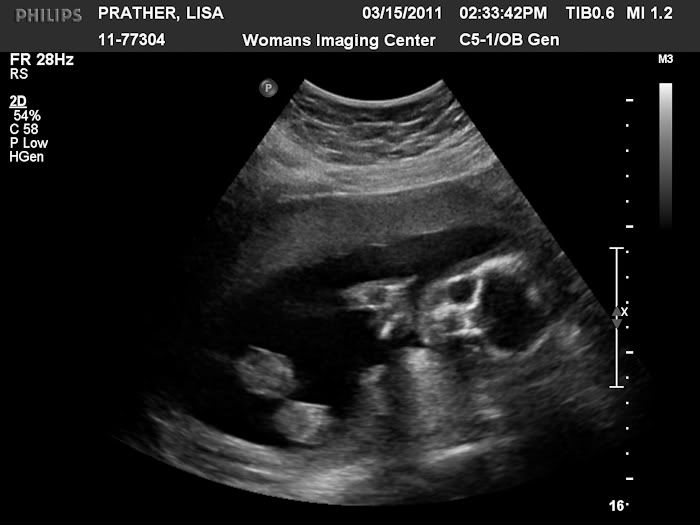

Today is our big ultrasound so I thought for today's throwback Thursday I would post Stephen's ultrasound pictures.  I was 20 weeks pregnant here.  This is the day we found out we were having a boy.

photo 020_web.jpg